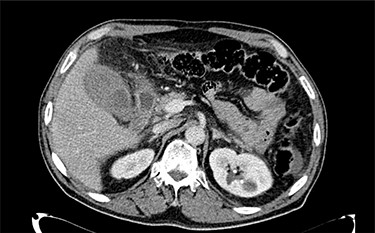

A 68-year-old male with arterial hypertension, dyslipidemia, cerebrovascular disease and a history of coronary heart disease, who had already done several percutaneous coronary interventions with stent placement, went to the emergency department with precordial pain and vomiting. At admission, he had an electrocardiogram in sinus rhythm with negative T waves V4–V6, DI and aVL. His blood test revealed leukocytosis 13 790/l with neutrophilia 11 600/l and polymerase chain reaction (PCR) 0.05 mg/dl, with normal cardiac markers. The pain improved with sublingual nitroglycerin. He was admitted and, on the next day, underwent a coronary angiography with angioplasty on the second diagonal of the anterior descending artery with stent placement due to a 70–90% lesion. During the procedure, he performed 5000 Units of heparin and 1 mg of isosorbide dinitrate. After the procedure, he was obnubilated and hypotensive, which improved with fluid challenge. New blood test was taken with evidence of increased leukocytosis to 17.540/l, PCR to 16.4 mg/dl, total bilirubin to 1.52 mg/dl, direct bilirubin 0.74 mg/dl, with normal aminotransferases and gamma-glutamyl transferase. Blood cultures, urine culture, chest X-rays were performed, and empiric antibiotics were started with piperacillin/tazobactam, and the consultation of general surgery was requested. In the evaluation it stands out that the patient was hypocoagulated and with dual antiplatelet therapy, with abdominal pain and defense in the upper quadrants. In blood test he had a slight increase in the international normalized ratio (INR) of 1.26 and in the prothrombin time. An abdominal ultrasound and CT scan (Fig. 1) was performed with evidence of gallbladder hydrops, with high-density contents suspected of thick mud, or hematic content, with a thickened gallbladder wall (~ 4–5 mm), with perivesicular fluid and perivesicular fat densification favoring the hypothesis of acute cholecystitis (Fig. 1). In this context, the patient underwent laparoscopic cholecystectomy on the same day with intraoperative diagnosis of acute gangrenous cholecystitis with intravesicular hematoma and hemoperitoneum (~450 cc) (Fig. 2 and video 1).

Abdominal CT scan showing the gallbladder with high-density contents.

Thus, for the diagnosis, it is important to confirm the presence of bleeding and hematoma in the gallbladder in addition to findings of cholecystitis [7]. For this, patients undergo ultrasound or abdominal CT to aid in the diagnosis. Ultrasound findings can show gallbladder wall thickening, intraluminal membranes and nonshadowing, nonmobile intraluminal echogenic material [8] and how it happened to our patient. In CT scan the findings usually described are dense content with or without layering, which may mimic sludge [9], and if contrast was used, an extravasation of contrast to the lumen may be observed in the arterial phase [10]. Despite these tests, the specific diagnosis of hemorrhagic cholecystitis is sometimes difficult by the similarity with other gallbladder pathologies such as acute cholecystitis [3].